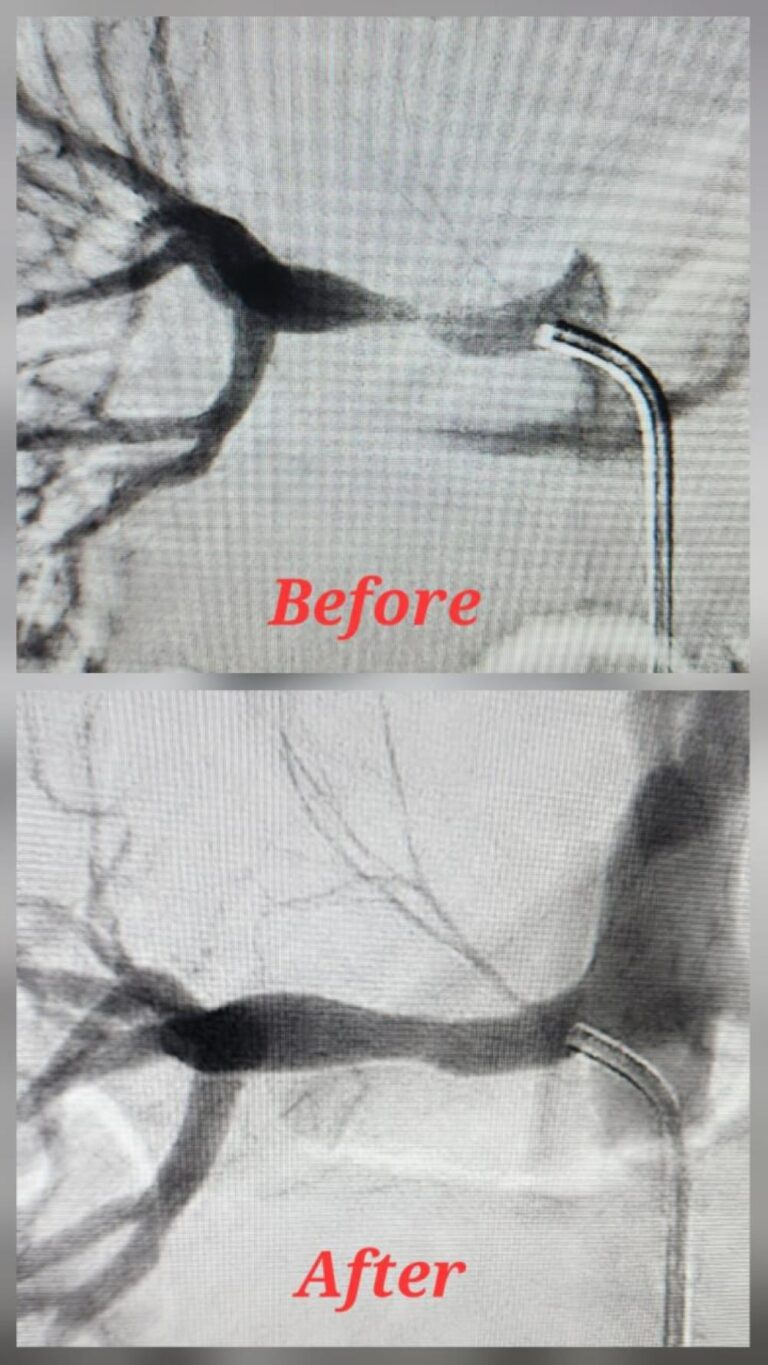

السعوديةقسطرة نادرة تنهي معاناة طفل من ارتفاع ضغط الدم في المدينة المنورةنوفمبر 2, 2025